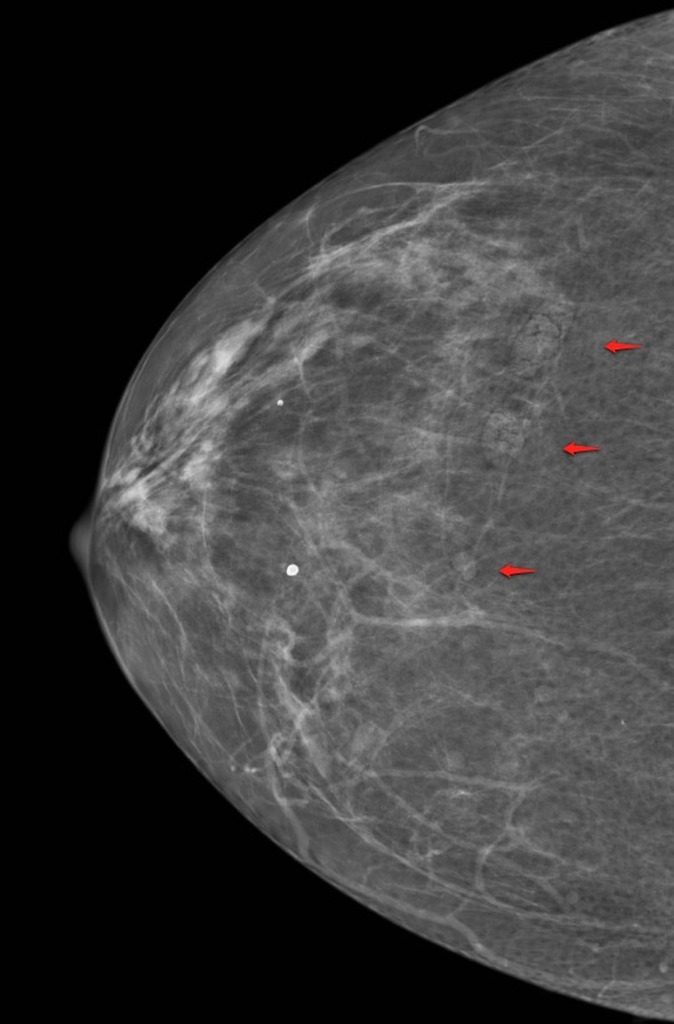

УЗИ молочных желез — информативный и безопасный метод диагностики, с помощью которого можно точно оценить состояние желез, обнаружить доброкачественные и злокачественные образования, уточнить диагноз. Это доступное по цене исследование безвредно и не несет лучевой нагрузки. Оно имеет большое значение в ранней диагностике заболеваний и нередко применяется в профилактических целях. На УЗИ может направить маммолог, онколог, эндокринолог, гинеколог.

Сделать УЗИ молочных желез можно в качестве первичной диагностики и для уточнения уже предполагаемого диагноза. Метод основывается на способности высокочастотных ультразвуковых волн с различной скоростью отражаться от тканей с разной плотностью.

С помощью ультразвуковой диагностики можно обнаружить следующие заболевания:

- воспалительные заболевания — мастит, абсцессы, лактостаз у кормящих женщин, мастопатии различного происхождения и типа — фиброзно-кистозные, диффузные и пр.;

- врожденные аномалии молочной железы;

- рак;

- кисты и доброкачественные опухоли;

кальцинаты.

Для оценки кровотока в тканях молочных желез используется доплерография. Данные, полученные в результате биопсии под контролем УЗ-аппарата, могут сказать о природе и характере образований в молочных железах.